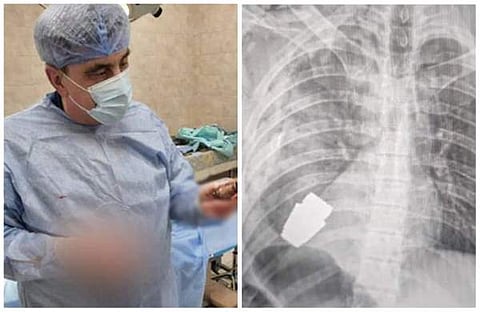

യുക്രൈന് സൈനികന്റെ നെഞ്ചില് തുളച്ചു കയറിയ ഗ്രനേഡ് സാഹസിക ശസ്ത്രക്രിയയിലൂടെ പുറത്തെടുത്ത് ഡോക്ടര്. പ്രവര്ത്തനം നിലച്ചിട്ടില്ലാത്ത ഗ്രനേഡ് ആണ് ഡോക്ടര് പുറത്തെടുത്തത്. ബഖ്മുട് പ്രദേശത്ത് റഷ്യന് ആക്രമണം ചെറുക്കുന്നതിനിടെയാണ് സൈനികന്റെ ശരീരത്തില് ഗ്രനേഡ് തുളച്ചു കയറിയത്.

ഏത് നിമിഷയും പൊട്ടിത്തെറിക്കുന്ന അവസ്ഥയില് ആയിരുന്നു ഗ്രനേഡ്. രണ്ട് സൈനികരുടെ സഹായത്തോടെ ആയിരുന്നു ശസ്ത്രക്രിയ. 'സൈനികന്റെ ശരീരത്തില് തുളഞ്ഞു കയറിയ വിഒജി ഗ്രനേഡ് ഞങ്ങളുടെ സൈനിക ഡോക്ടര് പുറത്തെടുത്തു. സൈന്യത്തിലെ ഏറ്റവും പരിചയ സമ്പന്നനായ സര്ജന് മേജര് ജനറല് ആന്ഡ്രി വെര്ബ ആണ് ശസ്ത്രക്രിയ നടത്തിയത്. ഗ്രനേഡ് ഏതുനിമിഷവും പൊട്ടിത്തെറിക്കാന് സാധ്യതയുണ്ടായിരുന്നു. അതിനാല് ഇലക്ട്രോണിക് സഹായമില്ലാതെ ആയിരുന്നു ശസ്ത്രക്രിയ.'- യുക്രൈന് സൈന്യം സാമൂഹ്യ മാധ്യമങ്ങളിലൂടെ അറിയിച്ചു.

പരിക്കേറ്റ സൈനികനെ മറ്റൊരു ആശുപത്രിയിലേക്ക് മാറ്റിയെന്നും അദ്ദേഹം സുഖം പ്രാപിച്ച് വരികയാണെന്നും യുക്രൈന് സൈന്യം വ്യക്തമാക്കി. അതേസമയം, എങ്ങനെയാണ് സൈനികന്റെ ശരീരത്തില് ഗ്രനേഡ് തുളച്ചതെന്നും എവിടെവെച്ചാണ് ശസ്ത്രക്രിയ നടത്തിയതെന്നും സൈന്യം വ്യക്തമാക്കിയിട്ടില്ല.